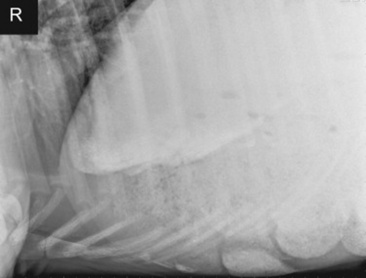

Abdominal radiography is useful to evaluate the small and large intestines for sand accumulation, enterolithiasis, impactions, or small intestinal disorders in foals. When sand is ingested, it generally will accumulate within the large colon along the ventral abdomen8 (Fig. 32-4). Radiography has been found to be a useful method to monitor the resolution of sand impactions after medical management; however, sequential examinations are needed to verify that the volume of sand has reduced.8 If the volume of sand is large enough, it is difficult to determine if an enterolith is present because of summation of the two lesions. Enteroliths are a solid concretion of mineral that usually forms around a nidus, such as a metallic foreign body (Fig. 32-5). The mineral composition is varied, as illustrated by the different opacities present within the enterolith. Radiographs have a 96.4% positive predictive value to detect enteroliths in high-prevalence areas. These enteroliths were generally found to be within the midabdominal radiograph, and 67% of small colon enteroliths caused large colon distention, which was also identified on radiographs.7 Impactions are more difficult to diagnose because usually there is just increased feed accumulation within the abdomen. Although no enterolith or obstruction is identified, granular material can be seen, usually within the ventral colon near the sternal flexure. This is because pelvic flexure impactions will cause the feed material to accumulate orad, causing distention of the left ventral colon (Fig. 32-6). Intestinal disorders such as functional ileus secondary to enteritis (Fig. 32-7) or obstruction secondary to intussusception or meconium impaction (Fig. 32-8) in foals can also be identified on abdominal radiographs. These images show large dilation of the small intestine, and differentiation between functional and mechanical ileus in foals is generally based on the size of the intestine and the volume of gas that is present.9 Evaluation of the abdomen using ultrasound may aid in qualifying the small or large intestinal motility as well as identifying the source of an obstruction if the determination on radiographs cannot be made.

image

Fig. 32-7 Standing lateral radiograph of a 1-day-old, premature quarter horse filly. Note the large amount of gas-distended intestine. Because of the large amount of small intestinal distention, functional ileus is the primary differential diagnosis.

Fig. 32-8 Standing lateral radiograph of a 2-day-old thoroughbred colt with a meconium impaction. Note the large amount of gas distention of the colon.